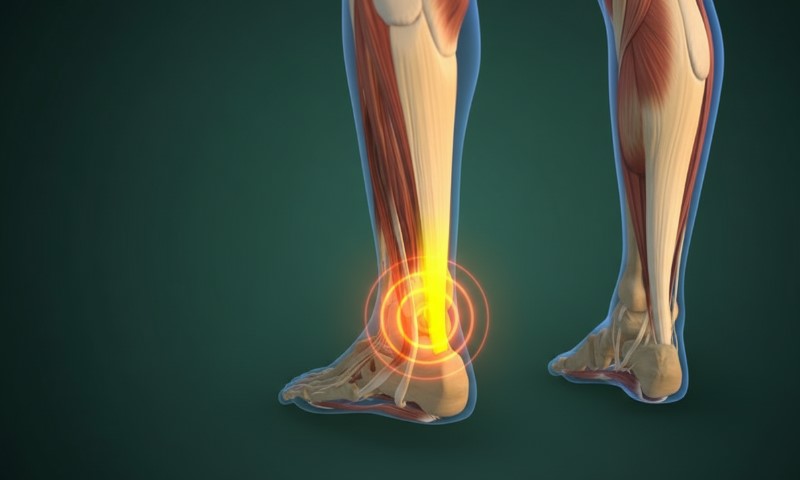

Achilles tendon rupture is a serious injury that affects mobility and athletic performance.

Healing tends to be slow due to the limited blood supply in the tendon and the high mechanical stress during walking and running.